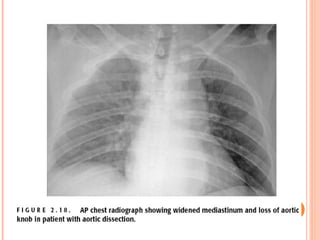

CXR PITFALLS   abnormal in 80-90% of cases Mediastinal widening- in 75% “ Calcium sign Aortic double density Disparity in caliber between ascending and descending aorta Localized bulge on the aorta Obliteration of the aortic knob NG tube, trachea or ETT displaced to the right Pleural effusions- common and usually on the left

• #42   CXR will be abnormal in 80-90% of cases Mediastinal widening- in 75% Hard to tell from tortuosity in chronic hypertension “ Calcium sign”- uncommon but highly specific intimal calcification >5 mm separated from outermost part of aorta Aortic double density Disparity in caliber between ascending and descending aorta Localized bulge on the aorta Obliteration of the aortic knob NG tube, trachea or ETT displaced to the right Pleural effusions- common and usually on the left Large effusions should cause suspicion of a leak or rupture